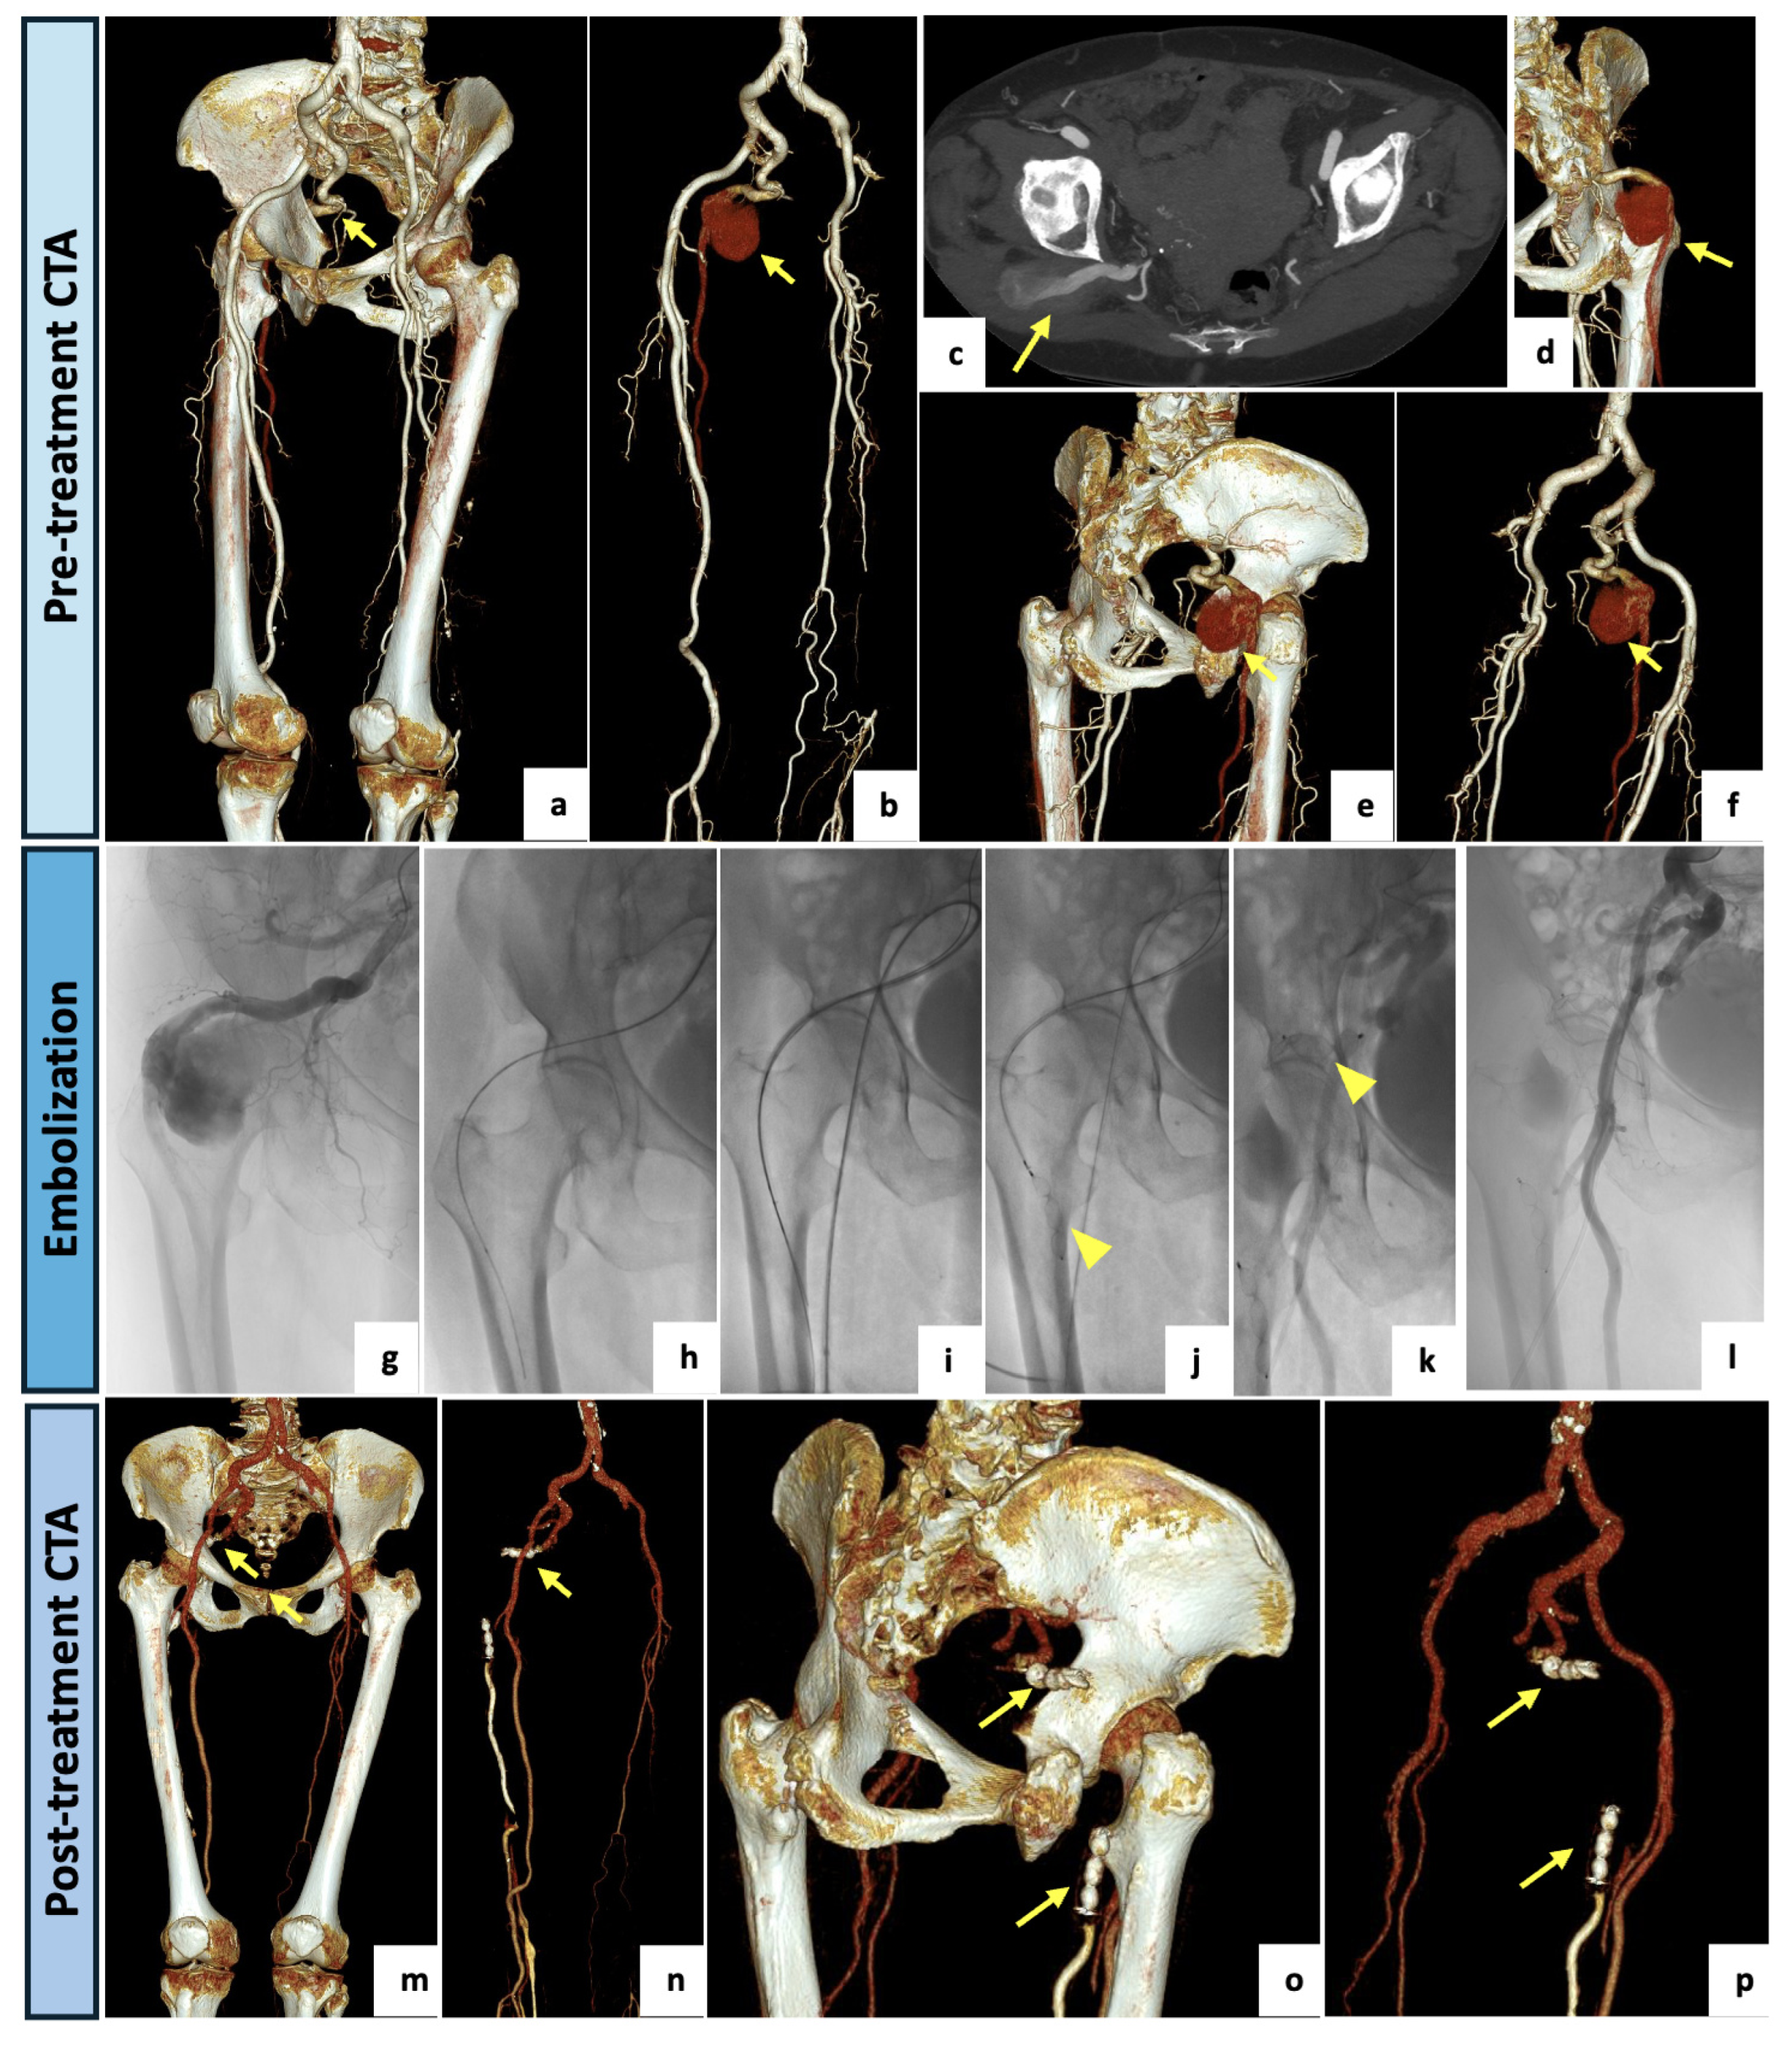

Figure 2.

(a) VR reconstruction of the preoperative CTA showing a right PSA originating from the internal iliac artery (arrow), continuing as a popliteal artery and associated with a normal SFA (type 1). (b–f) Three-dimensional reconstructions, with and without bone structures, and axial maximal intensity projections showing a huge aneurysmal degeneration (57 mm in the AP caliber) of the PSA in the posterior aspect of the thigh (arrows). (g) Intraprocedural selective angiography of the right PSA performed after obtaining a left humeral access with a 4F-sheat (60 cm), confirming a large aneurysm. (h,i) Intraprocedural images obtained after right common femoral artery access with a 6F-sheat and right PSA selective catheterization. (j,k) Aneurysm exclusion with “sandwich technique”: embolization through two vascular plugs deployed in the outflow and in the inflow vessel (arrowheads). (l) At final angiography, a nearly complete occlusion of the aneurysm (small residual slow flow) was documented. (m–p) VR reconstruction of postoperative CTA (1-month), demonstrating the complete exclusion of the PSA aneurysm. Both inflow and outflow were occluded by vascular plugs (arrows).